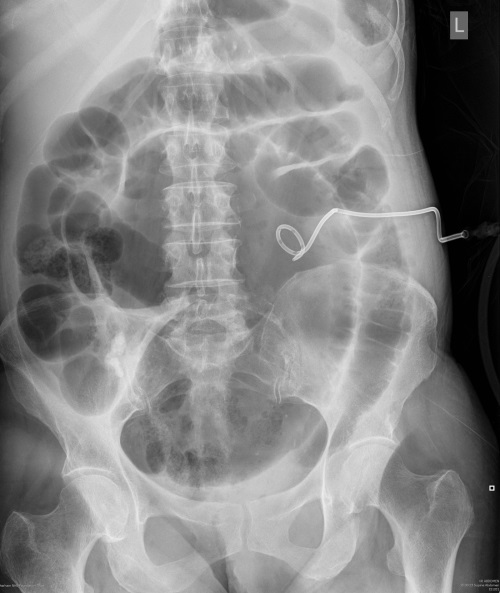

What does this AXR show?

You can see the typical ‘coffee bean’ appearance with three dense lines converging towards the site of obstruction (Frimann Dahl’s sign) in keeping with sigmoid volvulus.